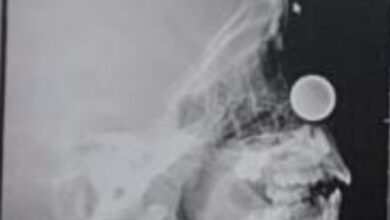

استخراج قطعة معدنية نقدية من أنف طفل السبع أعوام

أحوال – مكة المكرمة – نوال مسلم تمكن فريق طبي بمستشفى حراء العام عضو تجمع مكة المكرمة الصحي ، من إستخراج قطعة نقدية معدنية من أنف طفل يبلغ من العمر…